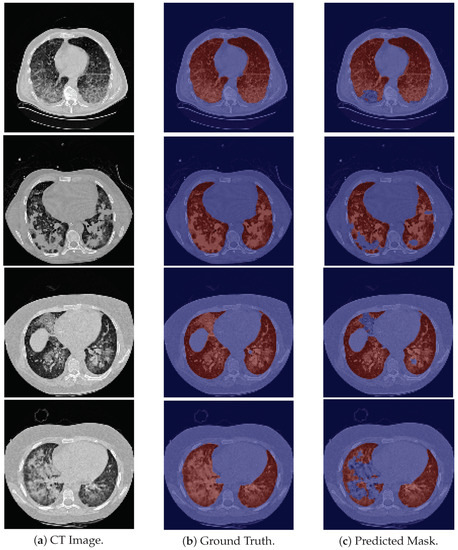

Regarding the HUG-ILD dataset, the model successfully segments the majority of scans and in some cases, it does not exclude pulmonary regions presenting a higher density. The model was also assessed on this dataset on a pattern level, i.e., each pattern was evaluated individually, to gain a better understanding of its behavior, and the results are presented in Table 5.

The results presented in Table 5 can be visually verified in Figure 3. For the specific cases of micronodules, bronchioectasis, emphysema, and some cases of fibrosis, the model is able to segment the entire lung area, as these are patterns which do not contain a higher contrast in tissues density (see respective examples on the first four rows of Figure 3). In general, those pathological cases showed a slightly better performance (Table 5).

In contrast, for cases of macronodules, reticulation, consolidation, ground-glass, and pneumocystis carinii pneumonia, the model presents a difficulty in performing such tasks in the regions of higher density (see last five examples (rows) of Figure 3). Besides that, the scans from this dataset include the trachea and other respiratory structures (apart from the lungs) in their ground truth, elements that are not identified by the model, and thus contributing to a lower metric (see rows two–five in Figure 3). Once again the model fails to identify the slices corresponding to the base of the lung (see the second row in Figure 6).

Figure 3. Examples of HUG-ILD images for pathological cases. The patterns of these images from top to bottom are, respectively, micronodules, bronchioectasis, emphysema, fibrosis, macronodules, reticulation with ground-glass, consolidation, ground-glass, and pneumocystis carinii pneumonia. For the last five examples, the model failed to segment part of the lung due to the pathological changes present in the image.

Applsci 12 01959 g003aApplsci 12 01959 g003b